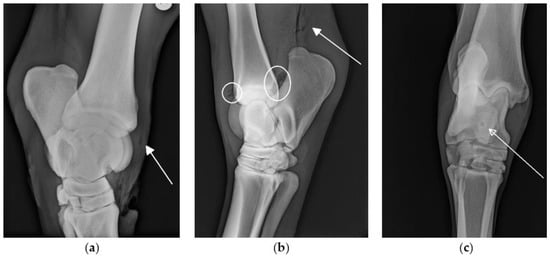

Radiographs were performed in 66/72 cases. In 10/66 cases, changes suggestive of SI, such as the presence of osteomyelitis or gas within a synovial structure (Figure 1) were seen on radiographs. In all 10 cases, a final diagnosis of synovial involvement was subsequently confirmed by additional diagnostic procedures (e.g., ultrasonography, synoviocentesis results). In 19/66 cases, synovial involvement was diagnosed based on other diagnostic procedures in the absence of radiographic changes to indicate SI. On the retrospective review of images, the radiographic identification of gas within bursae and tendon sheaths was subjectively more challenging than the radiographic identification of gas within the joints.

Figure 1. Radiographs of the tarsi with changes associated with SI (marked on the figures): Oblique latero-medial projection of the tarsus: (a) Air in the long digital extensor tendon sheath (arrow). (b) Latero-medial projection of the tarsus: air in the tarsocrural joint (circles) and subcutaneous air proximal to the calcaneous (arrow). (c) Dorsoplantar projection of the tarsus: round radiolucency at the level of the medial trochlea ridge of the talus (arrow) suggestive of osteomyelitis.